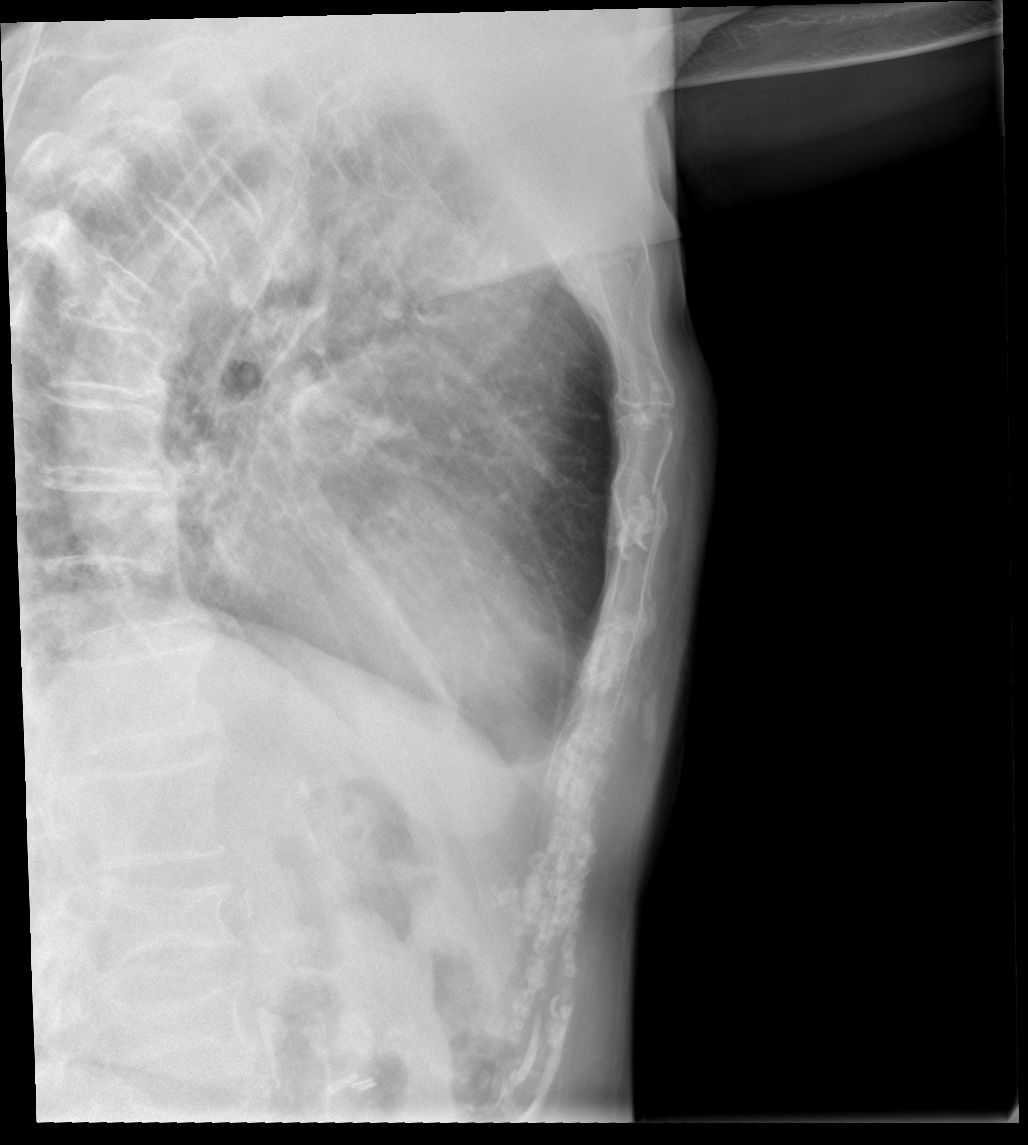

CASO: Febrícula y tos de 4 días de evolución.

Hallazgos:

- En la placa PA se observa una asimetría en los hilios pulmonares, el hilio izquierdo tiene una densidad aumentada.

- Tras examinar la placa lateral se observa un aumento de densidad en la columna que puede ser compatible con una condensación, es el signo de la desnificación vertebral.

SIGNO DE LA DENSIFICACIÓN VERTEBRAL: En la radiografía lateral normal, la densidad de la columna torácica tiende a disminuir desde la parte superior hasta el diafragma; la alteración de ese patrón por la presencia de una densidad superpuesta a la columna, indica la existencia de una consolidación pulmonar. Este signo adquiere especial valor cuando en la proyección posteroanterior la consolidación está oculta en el espacio retrocardíaco o en la base pulmonar.